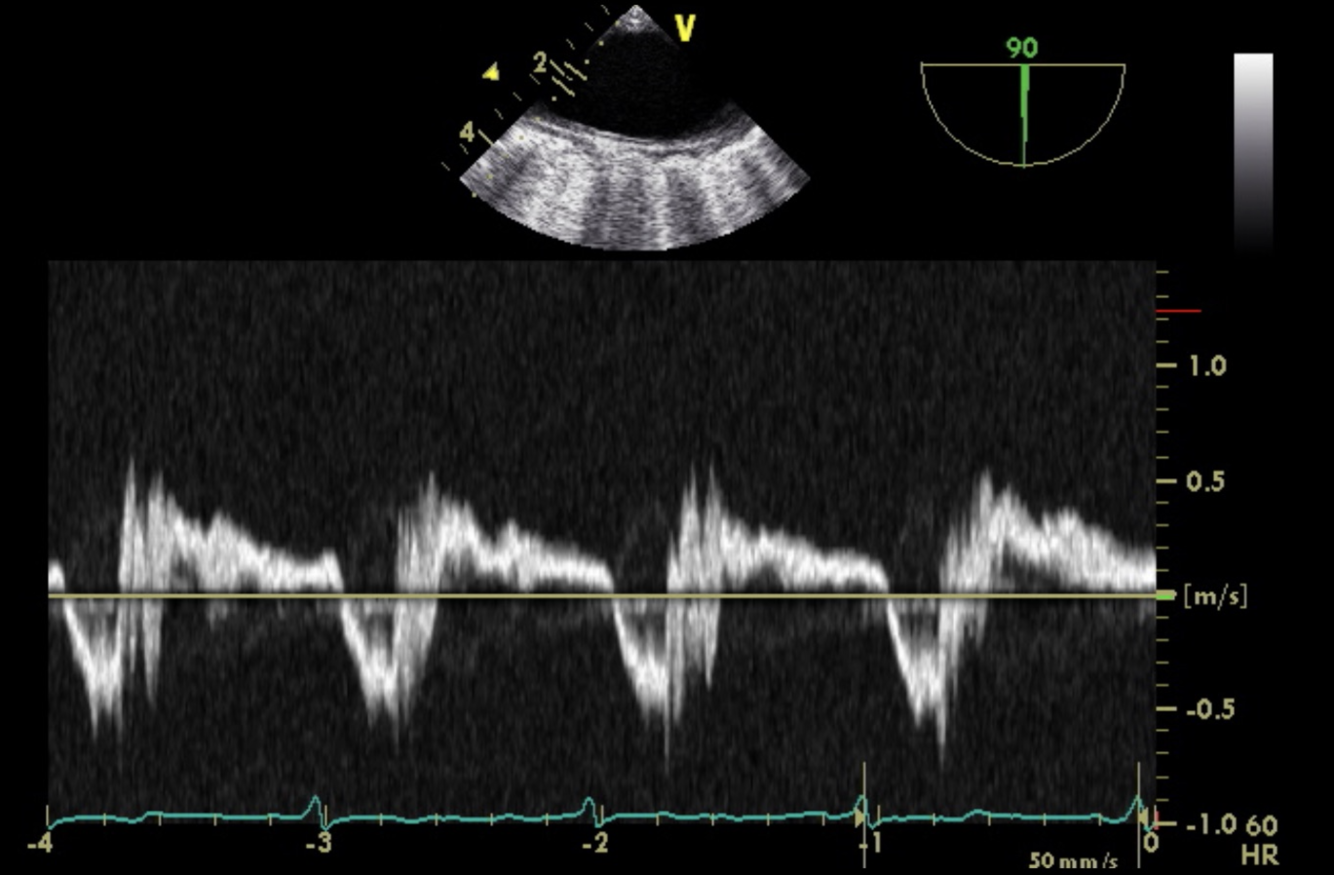

What is the Diagnosis?

Severe Aortic Insufficiency.

Flow reversal. Retrograde flow. Holodiastolic. In the Distal Aorta.